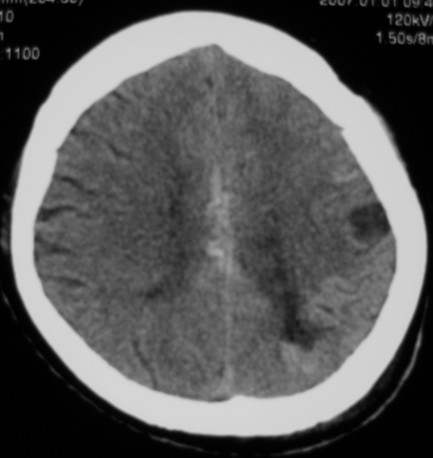

第一次ct片脑出血术后,出血吸收期。第二次ct 片左颞顶枕部及右颞顶部有脑回样高密度影。考虑珠网膜下腔出血。脑出血术后改变,脑出血恢复期 并脑积水。

第一次ct片脑出血术后,出血吸收期。第二次ct 片左颞顶枕部及右颞顶部有脑回样高密度影。考虑珠网膜下腔出血。脑出血术后改变,脑出血恢复期 并脑积水

两次的片都有,第二次比第一次的明显